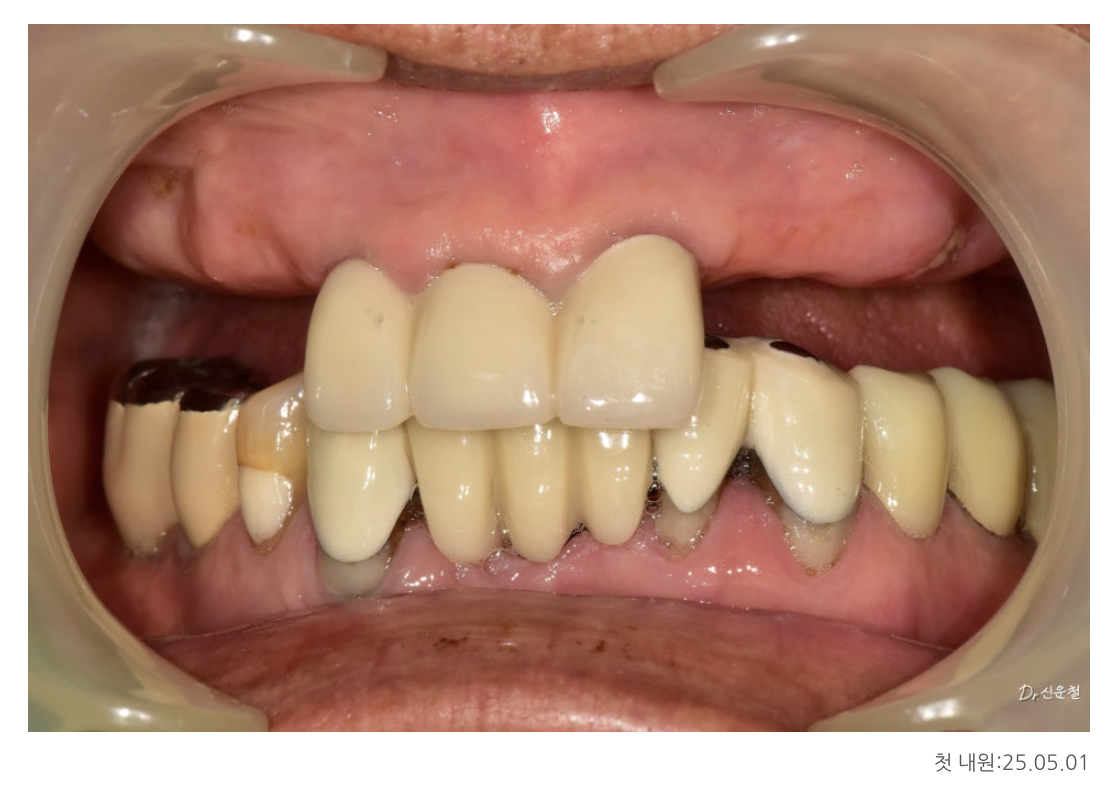

✔ 첫 내원 시 상태 (25.05.01)

앞니 세 개만 남아있는 상태

양쪽 어금니는 모두 상실

오래된 틀니 사용으로 잇몸뼈가 많이 닳아 있음